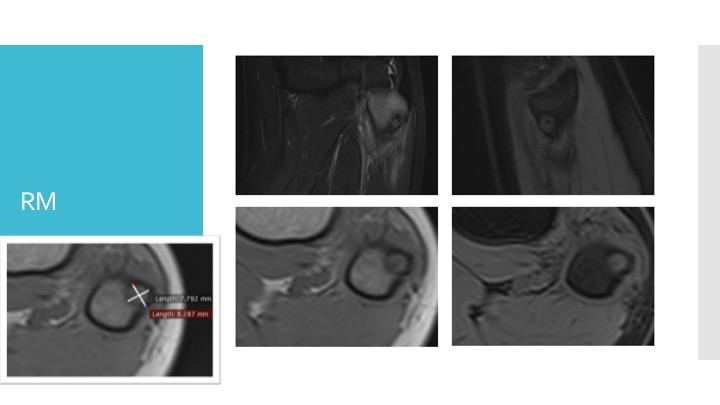

- Risonanza magnetica (RM): è un esame che utilizza campi magnetici per visualizzare sia le ossa che i tessuti circostanti.